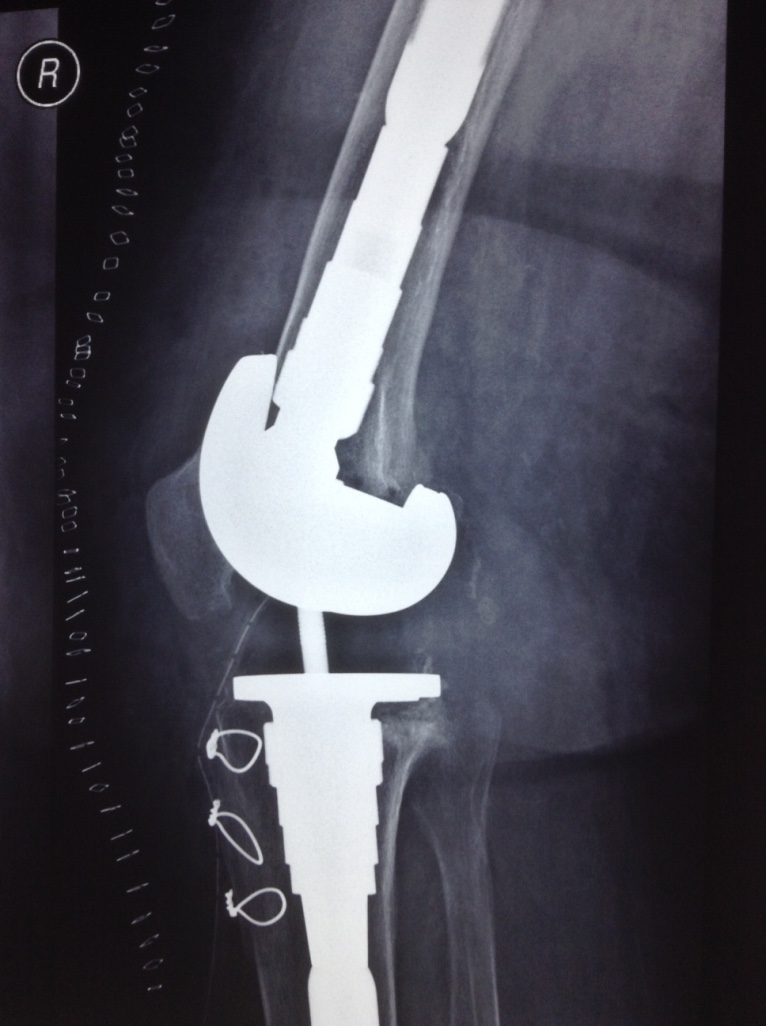

Revision Total Knee Replacement After a fructure

• Revision Total Knee Replacement After a fructure